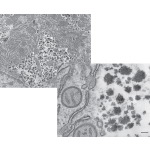

Electron Micrograph of Glycon In the Cytoplasm of a Hepatocyte